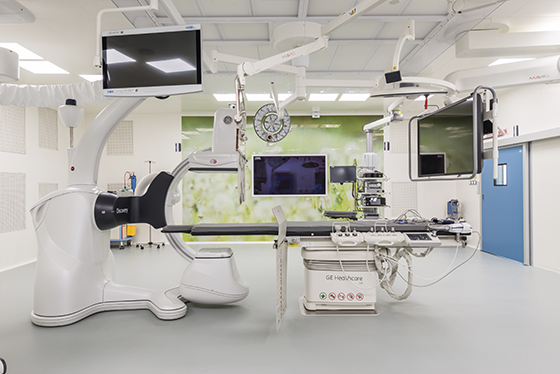

В институте онкологии Hadassah Medical Moscow проводится лечение злокачественной тимомы и опухолей средостения. В рамках нашей работы мы занимаемся хирургическим лечением, иммунотерапией, таргетной терапией, лучевой терапией и реабилитацией пациентов.

Передовая лаборатория

Наша собственная лаборатория, оснащённая самым передовым оборудованием и персоналом, позволяет за короткий срок качественно проводить любой вид лабораторного исследования связанный с тимомой.

Мультидисциплинарный подход

В нашей клинике в ведении каждого пациента с тимомами участвуют и взаимодействуют врачи разных специальностей: торакальные хирурги, химиотерапевты, лучевые терапевты, патоморфологи, медицинские генетики, радиологи и врачи смежных специальностей.